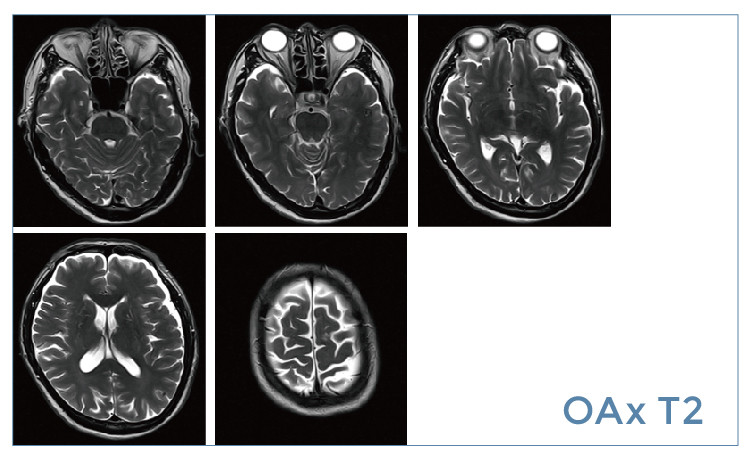

【朗润影像档案】磁共振影像病例分享(编号20190524)